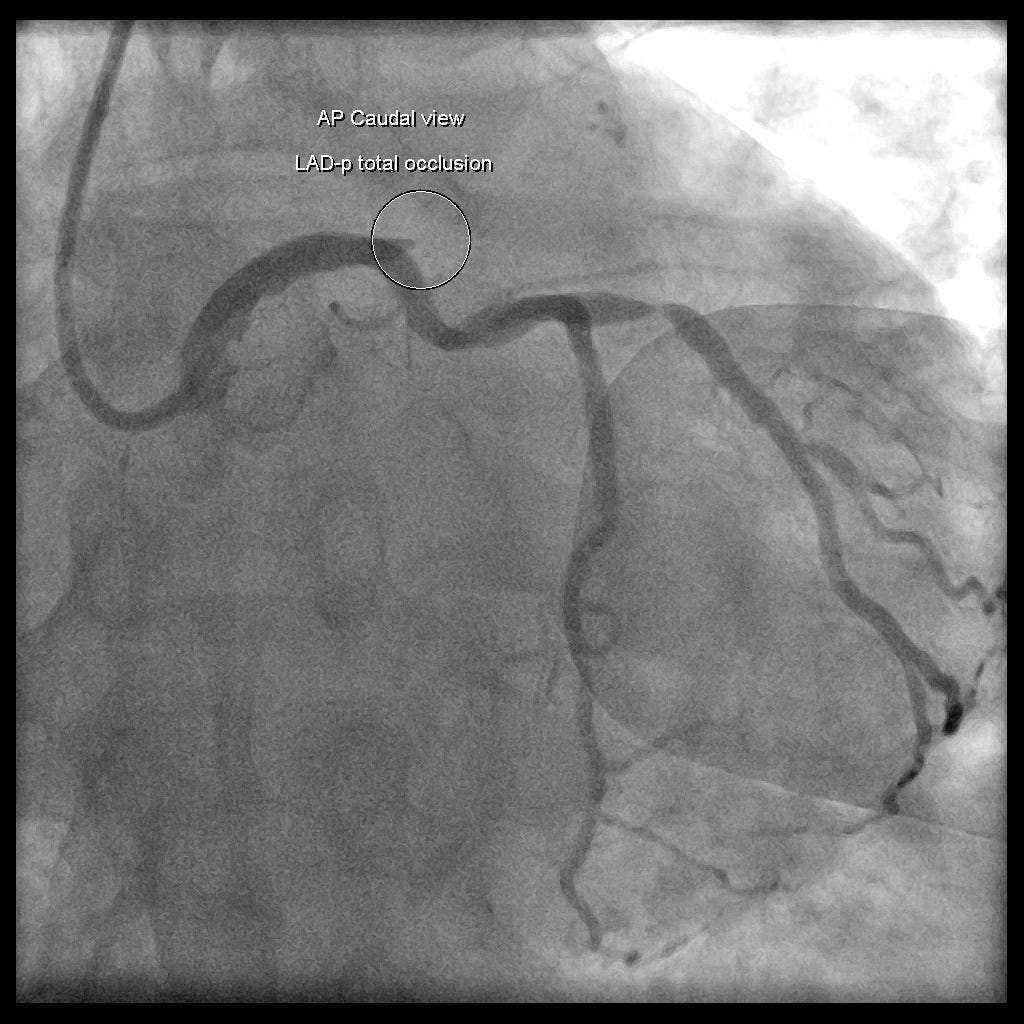

心導管報告:LAD-p total occlusion、RCA-p CTO